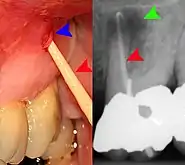

Clinical & xray correlation of pericoronitis

clinical shot of pericoronitis

An operculum (green arrow) over a partially erupted lower left third molar tooth. There is minimal inflammation and recurrent swelling.

xray of pericoronitis

A radiograph of the above tooth showing chronic pericoronitis, operculum (blue arrow) and bone destruction (red arrow) from chronic inflammation. Tooth is slightly disto-angular.

Pericoronitis is inflammation of the soft tissues surrounding the crown of a partially erupted tooth.[25] The lower wisdom tooth is the last tooth to erupt into the mouth, and is, therefore, more frequently impacted, or stuck, against the other teeth. This leaves the tooth partially erupted into the mouth, and there frequently is a flap of gum (an operculum), overlying the tooth. Bacteria and food debris accumulate beneath the operculum, which is an area that is difficult to keep clean because it is hidden and far back in the mouth. The opposing upper wisdom tooth also tends to have sharp cusps and over-erupt because it has no opposing tooth to bite into, and instead traumatizes the operculum further. Periodontitis and dental caries may develop on either the third or second molars, and chronic inflammation develops in the soft tissues. Chronic pericoronitis may not cause any pain, but an acute pericoronitis episode is often associated with pericoronal abscess formation. Typical signs and symptoms of a pericoronal abscess include severe, throbbing pain, which may radiate to adjacent areas in the head and neck,[21][26]:122 redness, swelling and tenderness of the gum over the tooth.[27]:220–222 There may be trismus (difficulty opening the mouth),[27]:220–222 facial swelling, and rubor (flushing) of the cheek that overlies the angle of the jaw.[21][26]:122 Persons typically develop pericoronitis in their late teens and early 20s,[28]:6 as this is the age that the wisdom teeth are erupting. Treatment for acute conditions includes cleaning the area under the operculum with an antiseptic solution, painkillers, and antibiotics if indicated. After the acute episode has been controlled, the definitive treatment is usually by tooth extraction or, less commonly, the soft tissue is removed (operculectomy). If the tooth is kept, good oral hygiene is required to keep the area free of debris to prevent recurrence of the infection.[21]:440–441